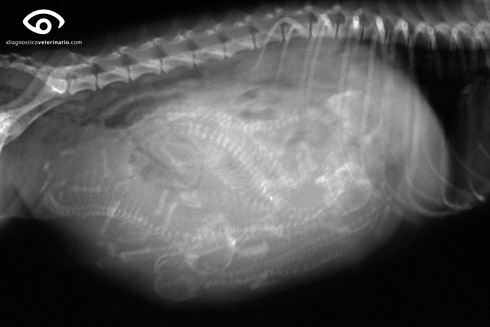

Para saber si hay gestación, hay que acudir al veterinario y él realizará una palpación abdomnal y a partir de los 20-25 días de gestación se puede hacer una ecografía y después de los 45 días una radiografía en la que veremos el número de cachorritos.

- Es conveniente hacer una radiografía el día 60 de la gestación para poder ver la colocación de los cachorros.